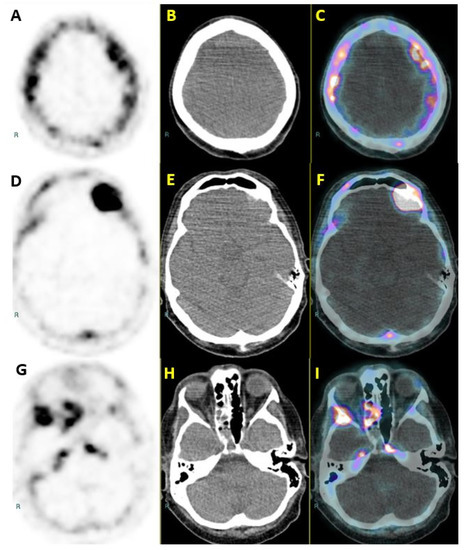

Figure 1. A 74-year-old man was referred to our center for a 18F-fluorocholine (18F-FCH) positron emission tomography–computed tomography (PET/CT). Nearly four years earlier the patient had been diagnosed in another hospital with metastatic prostatic adenocarcinoma (Gleason score 4 + 3, Ct2bN0M1 bone). The tumor was treated with external beam radiation therapy on the prostate bed and bone metastases (pubic bone and sacral lesion), and with androgen deprivation therapy and bisphosphonate. The disease was stabilized for nearly two years (according to the prostate specific antigen, PSA) and 18F-FCH levels taken as parameters. Despite the patient’s satisfactory clinical conditions, PSA was elevated to 937 ng/mL (previous value 82 ng/mL). The patient was started on enzalutamide 160 mg/day plus zoledronic acid 4 mg every 3 weeks, which resulted in a rapid decline of serum PSA levels (81 ng/mL). This biochemical response lasted for five months until PSA rose to 371 ng/mL. The patient was then prescribed 20 mg intra-venous docetaxel every three weeks in addition to 5 mg oral prednisone twice a day. Five months after the start of this regimen, the patient began to complain of a progressive and slowly worsening headache and diplopia. The patient’s Karnofsky performance scale (KPS) was 80. A restaging 18F-FCH PET/CT was scheduled and performed with a Siemens Biograph mCT nearly one hour after the intravenous administration of 163 MBq of 18F-FCH. The examination revealed an increased number of hypermetabolic lesions extensively involving the axial skeleton. Moreover, metabolic uptake was noted along the dura of the fronto-parietal convexities (transaxial PET, CT and fused PET/CT, Figure 1: A to C) in the left fronto-orbital region (transaxial PET, CT and fused PET/CT, Figure 1: D to F) and the right sphenoid region (transaxial PET, CT and fused PET/CT, Figure 1: G to I). These findings were strongly suggestive of meningeal metastatic implants. Since the seeding of prostate cancer metastatic cells in this location is highly unusual, a brain magnetic resonance examination was requested for a more detailed evaluation of these lesions. Unfortunately, the patient cannot be imaged due to claustrophobia.